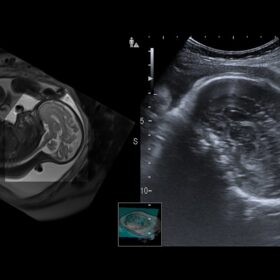

Ultrasound ARIETTA 850 SE – Image Gallery and Videos

Radiology CMUT Probe Whole Body